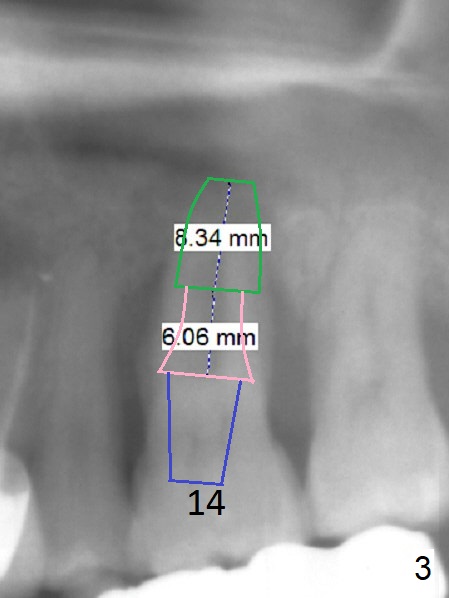

Abutment with 6 mm Cuff A 48-year-old man has mobile, symptomatic upper left 1st molar with severe gingival recession (Fig.1,2, particularly palatal). There appears no sinus floor. The thick gingiva (6 mm (Fig.3 pink)) will dictate a particular implant system. The long clinical crown suggests a long abutment (blue, 7 mm). After extraction and Clindamycin, use the smallest tap drill to initiate osteotomy until stability and sinus lift are achieved. PRF plug (1) and membrane (3) are to be prepared. Return to